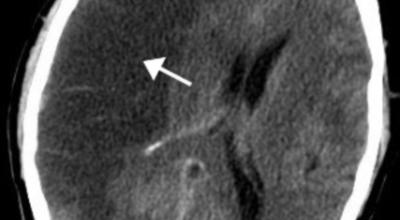

뇌출혈 전조증상을 놓쳐 뇌출혈이 발생하게 되면 발작 직후 안정을 취해야 합니다. 뇌부종을 가라앉히기 위해 약물 요법으로 고농도 포도당, 덱사메타존, 만니톨 등을 투약할 수 있고 뇌의 혈액 순환을 회복시키는 주사와 지혈제, 진정제 등을 사용할 수 있습니다. 혈종의 크기가 중등도 이상으로 마비 증세가 있으면 머리뼈에 작은 구멍을 내서 관을 넣어 혈종을 뽑아내는 수술을 시행할 수 있습니다.

혈압성 뇌출혈인 경우 혈종의 크기가 작으며 환자의 증상이 경미하면 약물 치료를 시행합니다. 혈종의 크기가 매우 크며 뇌가 심하게 부어오를 때는 응급으로 머리뼈를 절개해 혈종을 빠르게 제거해야합니다. 응급조치가 늦어지면 뇌압이 상승해 의식을 잃고 사망에 이를 수 있기 때문인데요 이렇게 증상이 심할 때는 수술이 잘 되었더라도 예후가 좋지 못할 때가 많다고 합니다.